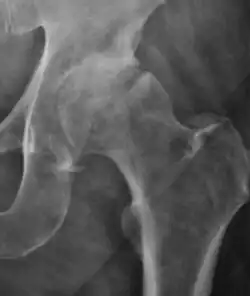

X-Ray

Projectional radiography ("X-ray") is currently useful not only in older people in whom osteoarthritis of the hip is suspected but also in younger people without osteoarthritis, who are being evaluated for femoroacetabular impingement (FAI) or hip dysplasia.[1]

Plain radiography allows us to categorize the hip as normal or dysplastic or with impingement signs (pincer, cam, or a combination of both). Besides these, pathologic processes like osteoarthritis, inflammatory diseases, infection, or tumors can also be identified (Figure 1).[1]

Figure 1.

-

Radiography in normal hip -

X-ray in pincer impingement type of hip dysplasia -

X-ray of cam -

Hip in osteoarthritis -

Septic arthritis

X-ray in pediatrics